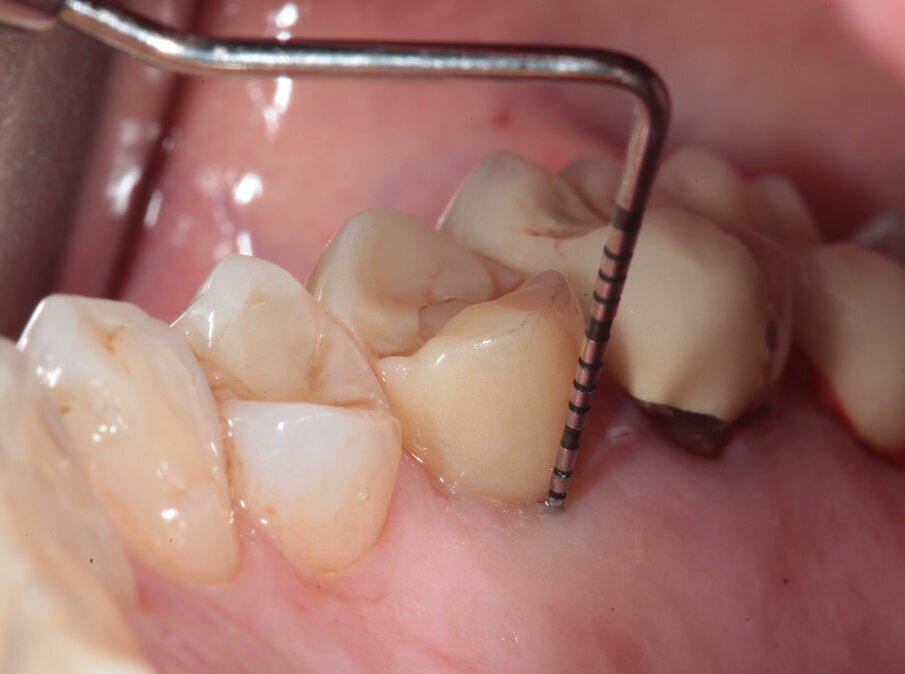

La paziente si presenta in visita lamentando mobilità e l’insorgenza di un dolore alla masticazione a carico dell’elemento 25. Clinicamente l’elemento presenta una corona in ceramica integrale realizzata anni prima (non ricorda quanti) presso altra sede, mobilità di II grado e sondaggio di 9 mm sul versante palatale.

Si presenta inoltre dolente alla percussione. Si riscontra anche l’assenza di risposta al test di vitalità dell’elemento 24, sul quale la paziente riferisce sia stata effettuata una medicazione endodontica da un collega come tentativo di risolvere la sintomatologia dolorosa a carico dell’elemento 25 (Figg. 1-3).